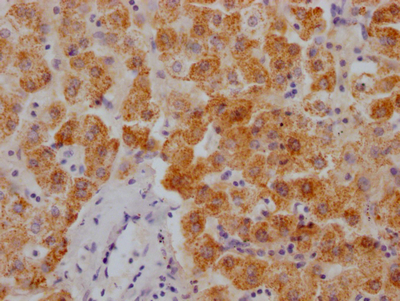

IHC image of CSB-PA892485ESR1HU diluted at 1:50 and staining in paraffin-embedded human endometrial cancer performed on a Leica BondTM system. After dewaxing and hydration, antigen retrieval was mediated by high pressure in a citrate buffer (pH 6.0). Section was blocked with 10% normal goat serum 30min at RT. Then primary antibody (1% BSA) was incubated at 4°C overnight. The primary is detected by a Goat anti-rabbit polymer IgG labeled by HRP and visualized using 0.05% DAB. Secondary antibody only control: uses 1% BSA instead of primary antibody